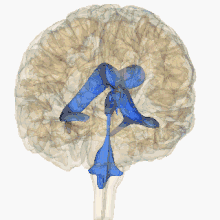

يحتوي المخ على مجموعة مكونة من أربعة بطينات (حجرات أو تجاويف صغيرة) كلها تحتوي على السائل الدماغي الشوكي فيما يعرف بالجهاز البطيني للمخ. تتصل البطينات الأربعة ببعضها وبالقناة المركزية الموجودة في منتصف الحبل الشوكي ويتم بداخل البطينات الأربعة وبشكل مستمر تكوين سائل مهم من سوائل الجسم يسمى السائل الدماغي الشوكي .

وفي ظروف أخرى يمكن أن ينشأ استسقاء الرأس عن تكوين السائل الدماغي الشوكي بمعدلات أكبر من الطبيعية فيحدث عدم التوافق بين إنتاج السائل النخاعي وامتصاصه. مما يسبب تراكمه داخل البطينات الدماغية أيضًا. بناءً على الآلية، استسقاء الرأس يمكن أن يصنف إلى استسقاء رأس متصل وغير متصل (انسداد). كلا الشكلين يمكن أن يكون إما خلقياً أو مكتسباً.